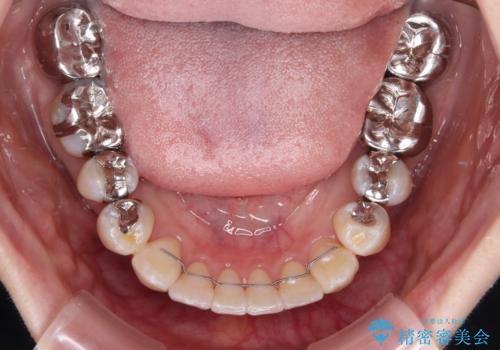

前歯を早々に仮歯に置き換えたことで、矯正治療に意欲的に臨んでくださいました。

口元が前方に突出することもなく、綺麗に仕上げることができました。